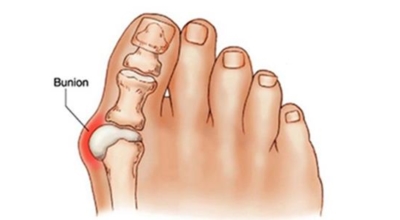

무지외반증이란

엄지발가락이 두번째 발가락 쪽으로 과도하게 휘고 엄지발가락과 관절을 이루는 중족골은 반대로 안쪽으로 치우치는 변형 되며 발가락이 발등 쪽으로 휘거나 회전(엄지발가락 축을 중점으로 내측으로 회전; 회내)하는 변형을 동반한 삼차원적인 변형을 말합니다.

무지외반증으로 인하여 변형이 심해지면 엄지발가락이 두 번째 발가락과 겹치거나 관절이 탈구되어 전반적으로 디디기 어려운 발이 되기도 합니다. 건강보험심사평가원의 무지외반증 환자 통계를 보면, 세대별로는 40대 이상에서 가장 많으며 성별로는 무지외반증 여성 환자 비율이 남성보다 월등하게 높았다고 합니다.